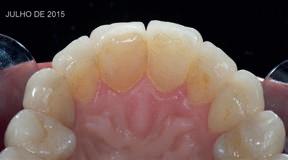

De assinalar que o desgaste do esmalte vestibular, proximal e incisal dos dentes preparados foi quase nulo e a preservação da vitalidade pulpar foi conseguida em todos os dentes (Fig. 3).

Decidiu-se descruzar a mordida e preencher os corredores vestibulares à custa de aderir umas facetas com um volume vestibular e um aumento do comprimento dos dentes bastante considerável (Fig. 4).

MARÇO 2011 MARÇO 2017